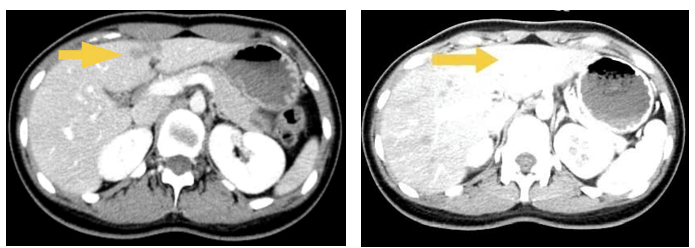

Hình 1: Nhu mô gan hạ phân thuỳ IV có ổ ngấm thuốc kém kích thước ~ 25x7mm. ( mũi tên vàng)

- Khối lớn vùng bẹn phải kích thước ~ 60x32mm, tỷ trọng hỗn hợp, ngấm thuốc sau tiêm, ôm quanh ~ 50% đường kính ĐM chậu ngoài kèm các hạch lân cận, hạch lớn kích thước ~ 14x8mm

Hình 2: Khối lớn vùng bẹn phải kích thước ~ 60x32mm, tỷ trọng hỗn hợp, ngấm thuốc sau tiêm,ôm quanh ~ 50% đường kính ĐM chậu ngoài ( mũi tên vàng)

- CT ổ bụng có tiêm thuốc cản quang: Gan:  Kích thước bình thường, bờ đều. Nhu mô đồng nhất trước và sau tiêm thuốc cản quang. Không thấy khối khu trú.

Hình 3: Nhu mô gan hạ phân thuỳ IV có ổ ngấm thuốc kém kích thước ~ 25x7mm. ( mũi tên vàng) nay đã mất

Vùng bẹn phải, nằm dọc bó mạch chậu ngoài và đùi chung có hình ảnh khối kích thước 32x68mm

Hình 4: Khối lớn vùng bẹn phải thay đổi kích thước không nhiều ( mũi tên vàng)